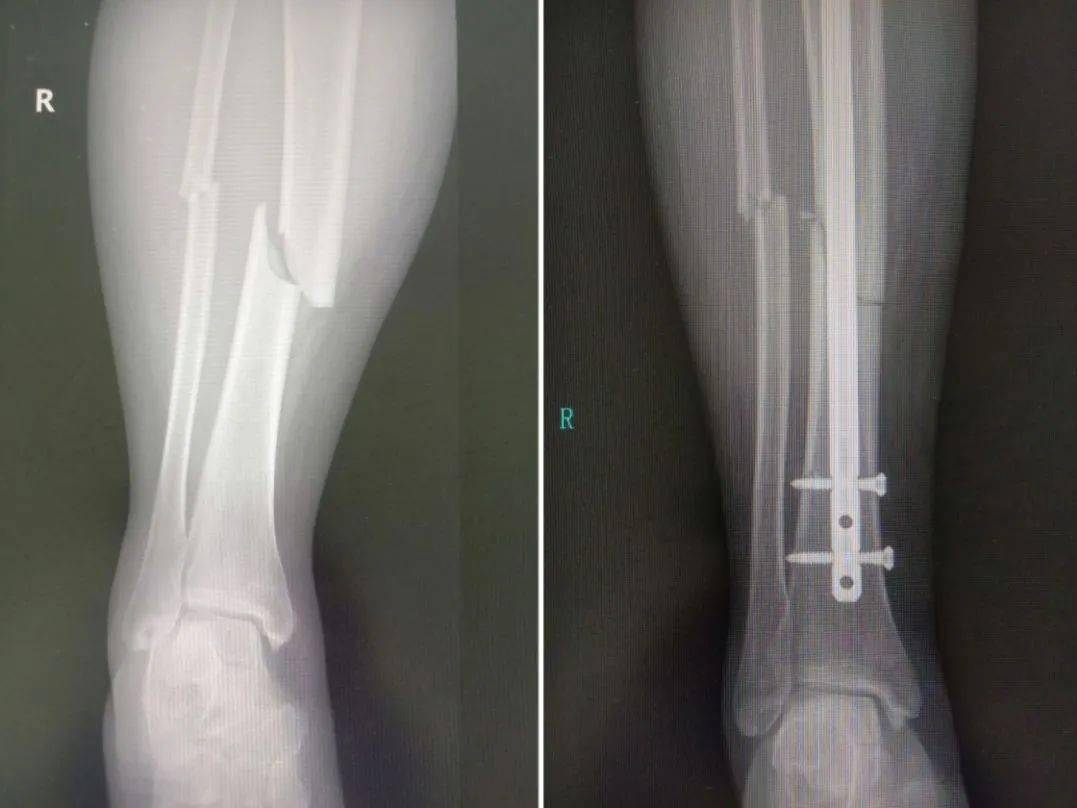

手臂被截断6段9节,断肢再植,全部存活!

图片尺寸640x1041